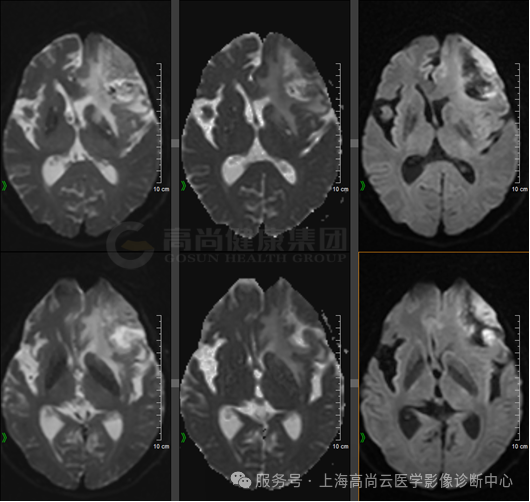

DWI

左顶叶可见团块状异常信号灶,大小约 38 mm×30 mm×35 mm,形态不规则,T1WI 呈稍低信号,T2WI 及 FLAIR 呈稍高信号,DWI 高信号,相应区域 ADC 呈稍低信号,ADC 值约 0.829×10-3 mm2/s,病灶内多发不规则囊变,相应区域 T1WI、DWI 呈低信号,FLAIR 呈低信号,T2WI 呈高信号,病灶局部 MRS 显示 Cho 峰增高,NAA 峰降低,Cho/NAA 比值约 3.45,增强时实性部分呈不规则、不均匀环形强化,部分呈延迟强化,相应区域灌注扫描显示 CBF 增高,邻近脑膜增厚、强化,周围可见大片水肿信号影环绕,邻近脑沟裂、脑池变浅,左侧脑室后角受压推移。

左额叶见不规则团块状异常信号影,边界欠清,大部分 T1WI 呈稍低、低信号,T2WI 及 T2 FLAIR 呈等稍高信号,内见点片状低信号,DWI 呈高信号,相应区域 ADC 呈稍低信号,ADC 值约 0.793 ×10-3 mm2/s,最大横截面大小约 44 mm×55 mm,病灶后部 T1WI 呈低信号,T2WI 呈高低混杂信号,FLAIR 呈稍低等混杂信号,SWI 呈明显低信号,DWI 以低信号为主,病灶周围见大片水肿信号影环绕,邻近侧脑室明显受压,左额部中线结构略右偏,增强后病灶呈明显不均匀强化,内可见不规则无强化坏死区,强化区域灌注扫描 CBF 增高,MRS 显示局部 Cho 峰明显升高,NAA 峰明显升高,Cho/NAA 比值约 87.02,出现 Lip 峰及 LAC 峰。3D T1WI 增强显示左侧额叶病灶邻近脑膜增厚强化;另外右侧颞窝底部可见小条状强化灶。